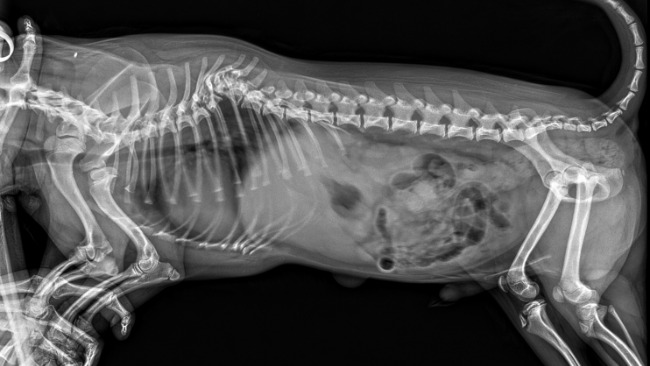

Niestety, na początku stycznia zaczął mieć problem z tylnymi nóżkami - zaczęły mu dziwnie uciekać. Podejrzewano zapalenie nerwów ale gdy mimo leków stan się pogorszył zrobiono mu RTG na którym widać było poważną wadę kręgosłupa. Powiedziano nam, że jedynym ratunkiem dla Blue jest operacja o ile znajdziemy neurochirurga, który podejmie się tak poważnej operacji.

Znaleźliśmy. Po zrobieniu tomografii komputerowej i konsultacji z neurochirurgiem okazało się, że Blue urodził się już z rozwojową wadą kręgosłupa odcinka piersiowo-lędźwiowego. Powoduje ona ucisk na rdzeń co z kolei prowadzi do problemów z koordynacją tylnych kończyn a z czasem doprowadzi do całkowitego paraliżu.